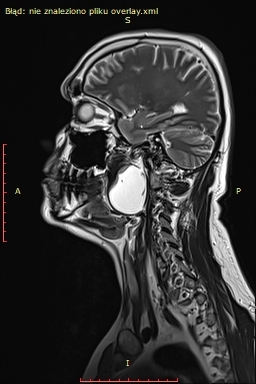

Badanie rezonansu magnetycznego wykazało (widoczne na zdjęciu) u pacjenta obecność dużej zmiany torbielowatej w przestrzeni przygardłowej po stronie lewej o wymiarach 54x42x38 mm. Zmiana miała postać torbieli zawierającej jednolity płyn, z pogrubiałą, postrzępioną wewnętrzną ścianą i gładką powierzchnią zewnętrzną. Torbiel powodowała przemieszczenie i ucisk okolicznych struktur. Biopsja aspiracyjna cienkoigłowa sugerowała torbiel boczną szyi.